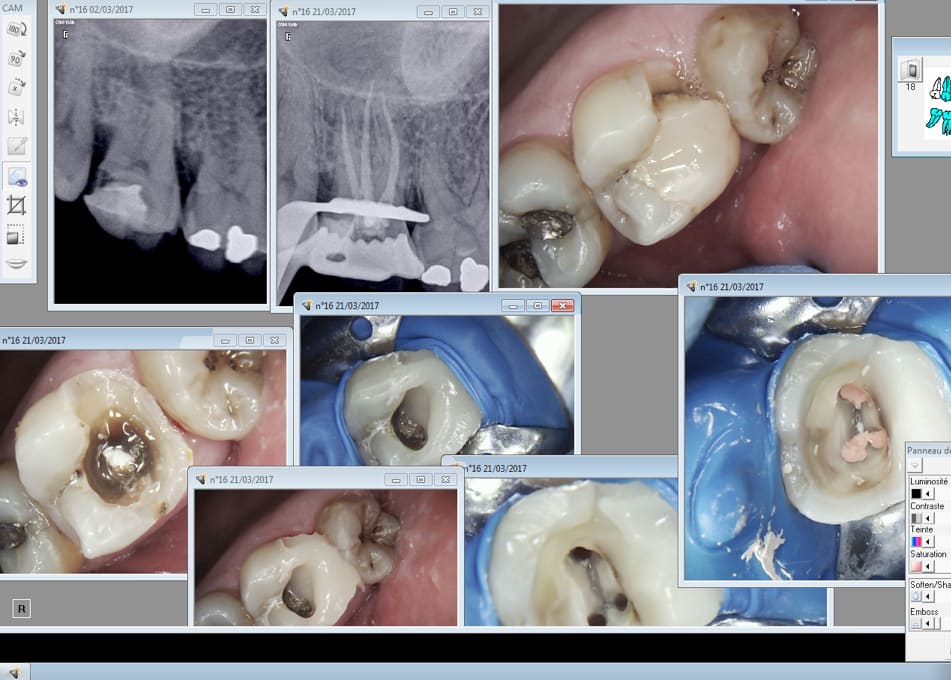

Cette patiente était ma dernière de la journée..... Donc parfaitement détendu j'ai eu le temps de bien l'éclairer. On vire le compo cassé photo et explication :

Voyez si on s'arrete là on peut faire un onlay et garder votre dent vivante.....

C'est 400 euros remboursés 40 par la sécu + votre mutuelle il vous reste 360 euros à charge.

C'est trop cher. Ah ?

Soit je remplis le trou avec le meme composite que celui avec laquelle j'ai déjà reconstitué la partie arrière de votre dent ( on va l'ancrer avec une vis dans une racine, ca ne sera pas plus solide mais il faut bien que je becte) on fait une couronne en céramique : il vous en coutera 580 euros remboursés 400 euros par la sécu et votre mutuelle. Donc 180 euros à charge.....

C'est encore trop cher docteur......

Ah ? Bon comme je n'ai pas qu'un tour dans mon sac je vais vous proposer LA solution à vos problèmes.

On rase tout ce qui reste, il ne va plus rester que la racine et on va y mettre un faux moignon en métal et une céramique. ca vous coutera 690 euros tout remboursé par votre sécu et votre mutuelle : 0 de reste à charge.

Vous voyez docteur, quand vous voulez........-)))))

Et voilà comment on passe de ca à ca ! -)

Magnifique le meilleur système de santé au monde ! -)))